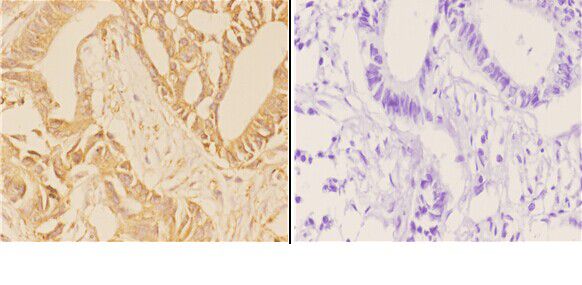

Facts about Broad substrate specificity ATP-binding cassette transporter ABCG2.

Xenobiotic transporter that may play an important role in the exclusion of xenobiotics from the brain. Appears to play a significant role in the multidrug resistance phenotype of many cancer cell lines.